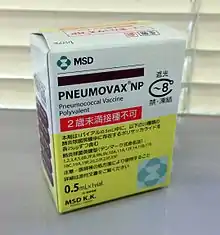

Prévention

Il existe plusieurs types de vaccins antipneumococciques :

- le vaccin conjugué, immunisant pour 13 sous-types (sérotypes) de pneumocoque (Prevenar 13). Aux États-Unis, l'utilisation à grande échelle de ce vaccin, chez les jeunes enfants, a entrainé une forte baisse des infections invasives à pneumocoques (sérotypes contenus dans le vaccin), chez les enfants vaccinés, et plus globalement des pneumonies nécessitant une hospitalisation[13], mais aussi, dans une moindre mesure, chez les enfants non vaccinés, dans la population générale et les plus de 50 ans. En France, la vaccination est obligatoire (depuis 2018) pour tous les nourrissons dès l'âge de deux mois. Pour les enfants de plus de deux ans, la vaccination est recommandée lorsqu'il existe une maladie favorisant les infections à pneumocoque[14] : brèches cérébroméningées, asplénie, déficit immunitaire, cardiopathies congénitales cyanogènes, pneumopathies chroniques sauf asthme et diabète. Ce vaccin n'a pratiquement pas d'efficacité sur la prévention des otites ;

- le vaccin polysaccharidique, immunisant pour 23 sous-types de pneumocoque et apparu en 1983, utilisé dans les situations à risques, en vaccination de l'adulte et de l'enfant de plus de cinq ans (voir ci-dessus) (Pneumo 23). C'est ce type de vaccin qui est recommandé par l'OMS dans les indications précisées[15]. Son efficacité réelle est toutefois, controversée[16]. Au Royaume-Uni, le , les autorités ont recommandé l'abandon du vaccin polysaccharidique en vaccination de routine pour les plus de 65 ans[17]. Elles sont revenues sur leur décision depuis, confirmant l'intérêt de ce vaccin chez les plus de 65 ans ()[18].